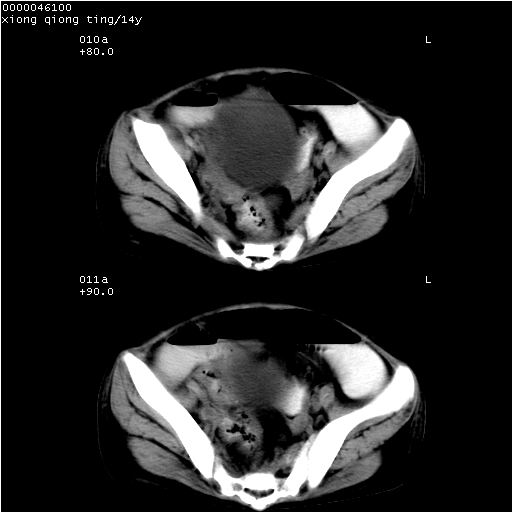

中下腹及盆腔ct轴位平扫+增强扫描(层厚10mm,螺距1.0,重建间隔10mm),图像如下:

(注:患儿检查当日上午9时口服胃肠道对比剂,下午3时许行ct扫描检查,未行对比剂直肠保留灌肠,检查当日患儿腹泻)

中下腹及盆腔ct轴位扫描(ps+ce)提示:腹部肠管明显充气扩张,并见数个不同宽度之气液平面;疑不全性肠梗阻或肠郁张。临床会诊考虑为患儿腹泻,肠郁张所致;后来未经特殊处理,患儿大便恢复正常,亦无腹胀。